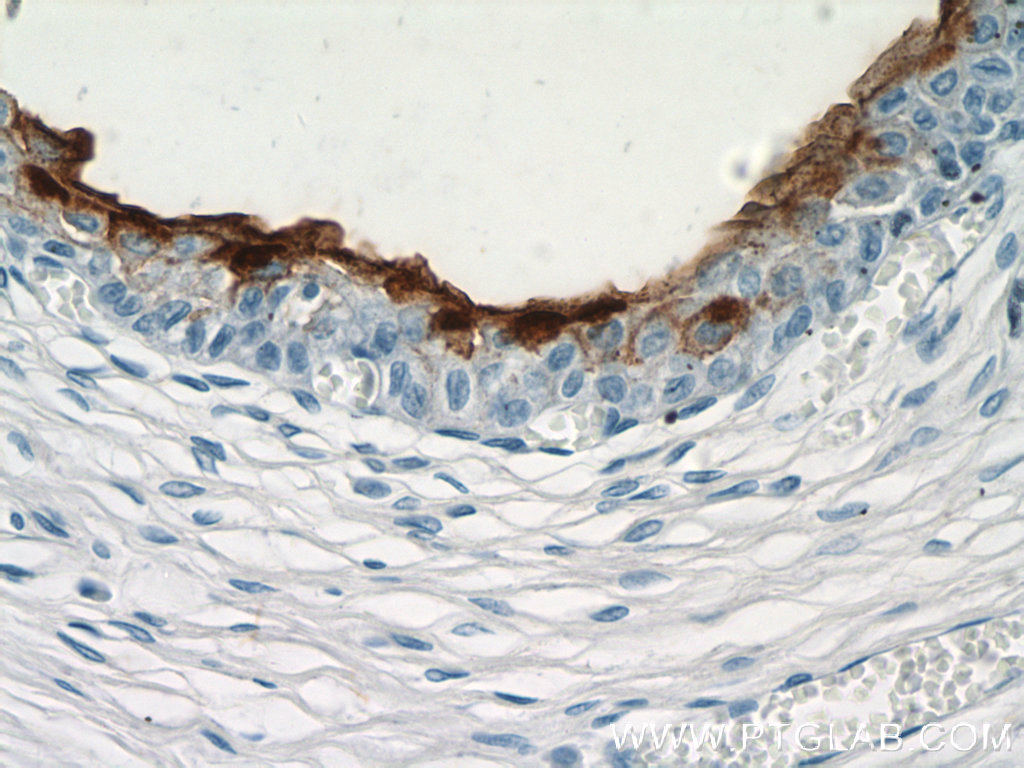

使用范围: WB,ELISA,IHC-P,IHC-F,IF

UPK3B抗体Applications